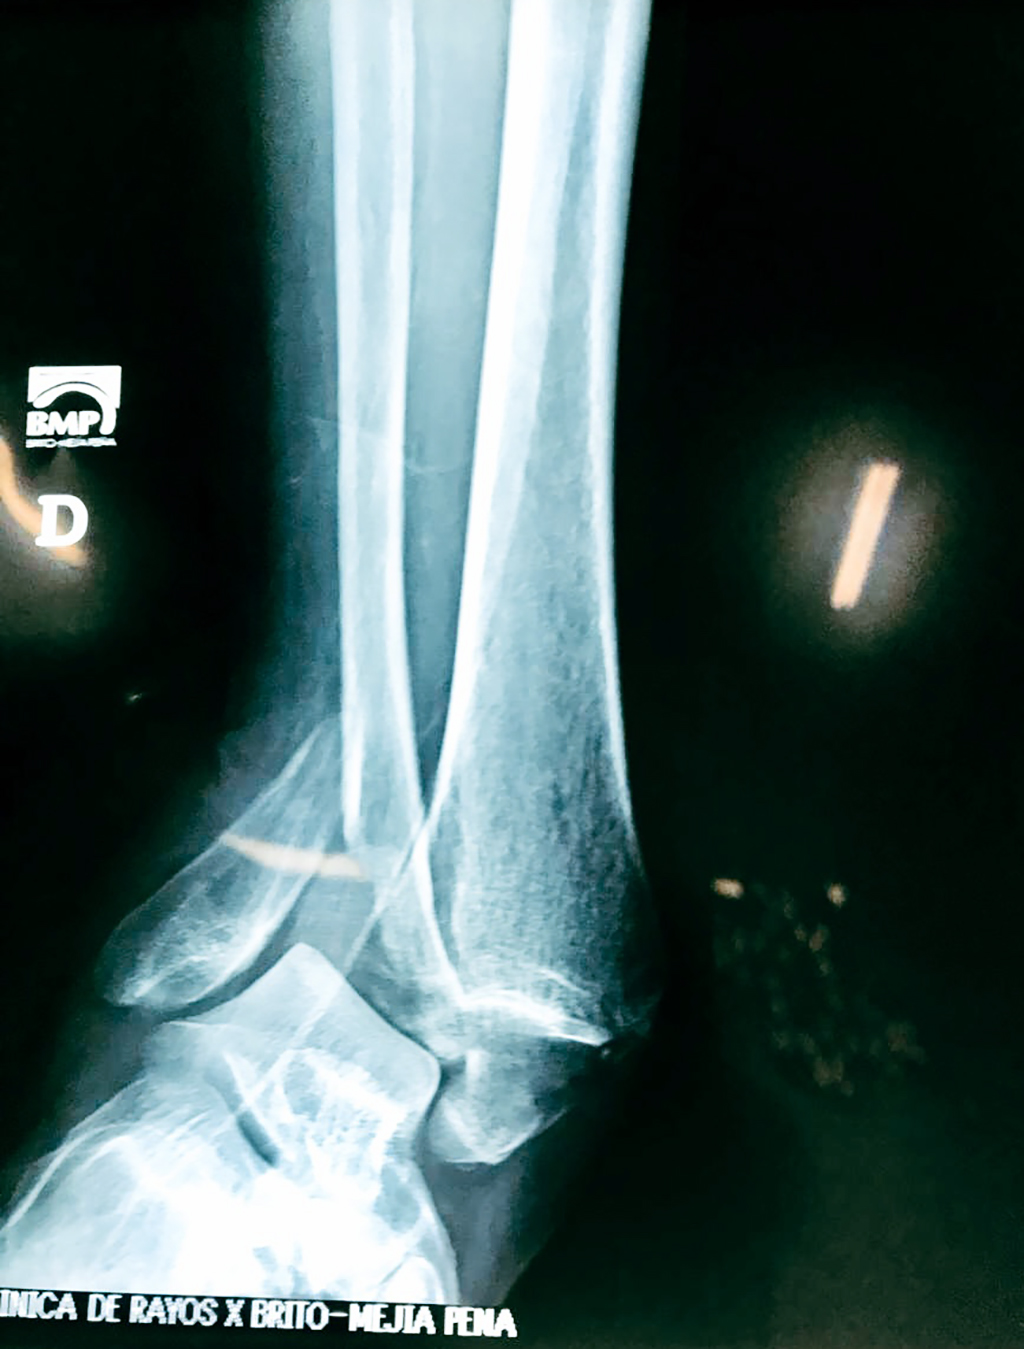

Una fractura de tobillo es la rotura de uno o más de los huesos del tobillo. Estas fracturas pueden ser:

Algunas fracturas de tobillo pueden requerir cirugía si:

Cuando se necesita cirugía, es probable que esta implique el uso de clavijas de metal, tornillos o placas para sostener los huesos en su lugar mientras la fractura se consolida. Los elementos de soporte pueden ser temporales o permanentes.